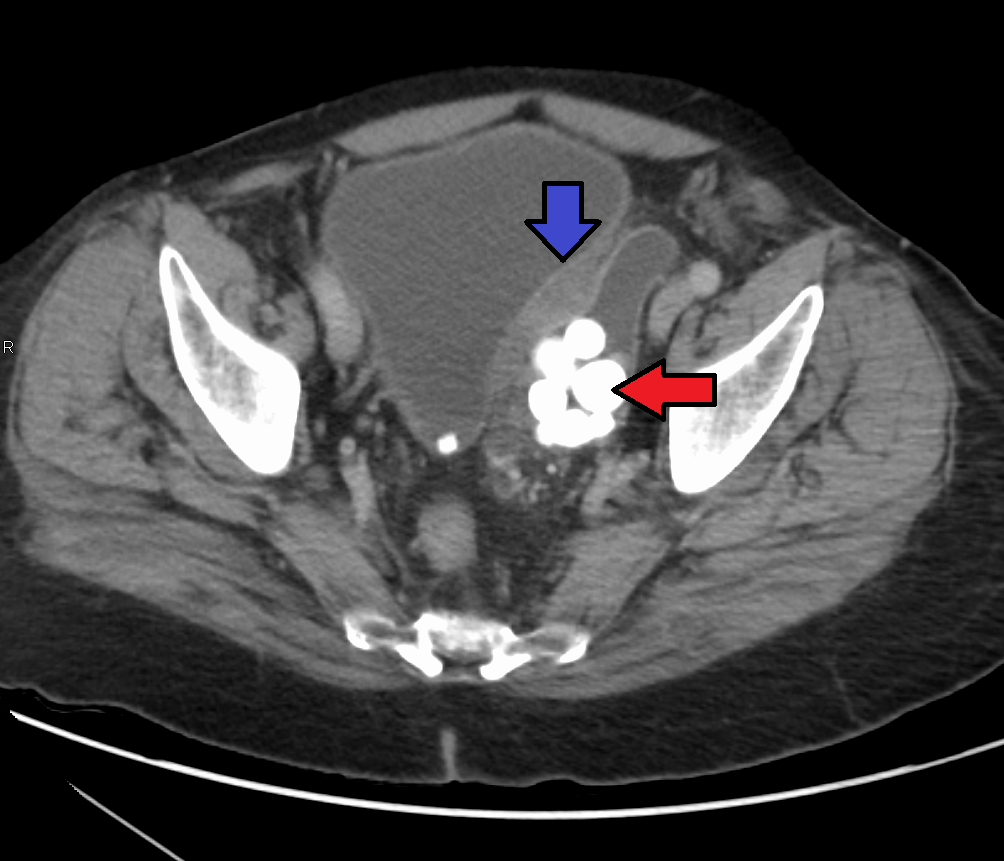

방광경 검사를 통해 내시경으로 방광 내부를 직접 관찰할 수 있다. 또한, CT, MRI 등 영상 검사를 통해 종양의 위치, 크기, 전이 여부를 확인한다. 방광경 검사 중 의심되는 부위의 조직을 채취하여 현미경으로 암세포를 확인하는 조직 검사도 진단에 활용된다. 분자 유전학적 검사를 통해 암세포의 유전적 특징을 분석하여 진단 및 치료에 활용하기도 한다.